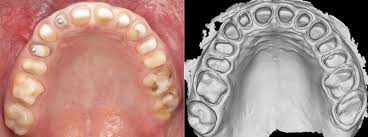

Sai lầm trong lấy dấu và đổ mẫu

Lấy dấu không chính xác dẫn đến độ sát khít kém, làm răng giả dễ bị rơi hoặc gây loét niêm mạc do áp lực phân bổ không đều. Việc không sử dụng vành khít đúng cách là nguyên nhân chính khiến phục hình mất lưu giữ.

- Răng giả bị sắp lệch khỏi đỉnh sống hàm làm mất sự ổn định khi ăn nhai.

- Không thiết lập được khớp cắn thăng bằng, dẫn đến hiện tượng bập bênh khi bệnh nhân thực hiện các vận động hàm sang bên.

Lưu ý: Việc đánh giá kỹ lưỡng tình trạng tiêu xương sống hàm của bệnh nhân trước khi bắt đầu là yếu tố bắt buộc để lựa chọn loại phục hình phù hợp.